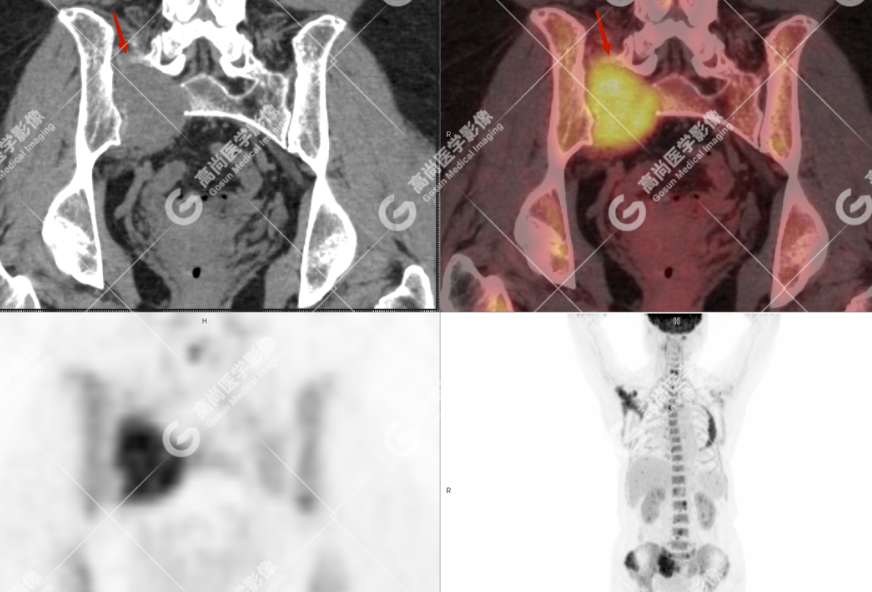

颅骨、寰椎前弓左侧份、第 6 颈椎、双侧肩胛骨(右侧为著)、左侧第 4 肋骨、第 1 胸椎、第 4 胸椎、第 2 腰椎及附件、第 4 腰椎及附件、骶骨、右侧髂骨、左侧坐骨结节、左侧股骨颈、双侧股骨小转子等均不同程度骨质吸收、破坏,其中右侧肩胛骨、左侧第 4 肋骨及骶骨右侧份软组织肿块影形成,上述病变均考虑恶性肿瘤(血液系统来源,多发骨髓瘤可能性大),建议右侧髂骨翼穿刺活检明确。

(4)PET-CT 影像表现:在溶骨性破坏区出现相重叠的 18F- FDG 高代谢区;通常呈弥漫性高代谢区。